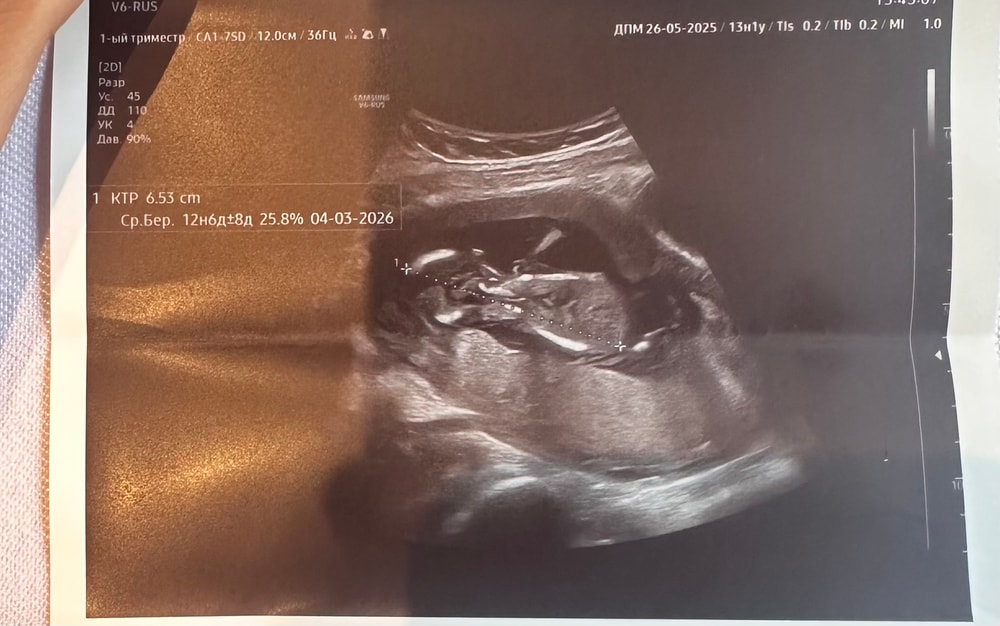

врач сначала измерила в одном положении -65 мм, я говорю маловато - на прошлой был 63 мм. Она говорит а мы сейчас еще по-другому измерим и там уже 79 мм.

Первое фото больше похоже на правду. Второе как головка у него к груди поджата и наискось измерили.

Алиса, как по мне, там где малыш распрямился, там и верно. А на втором он лежит калачиком, спал наверное, головку и ножки поджал, вот и намерили 65